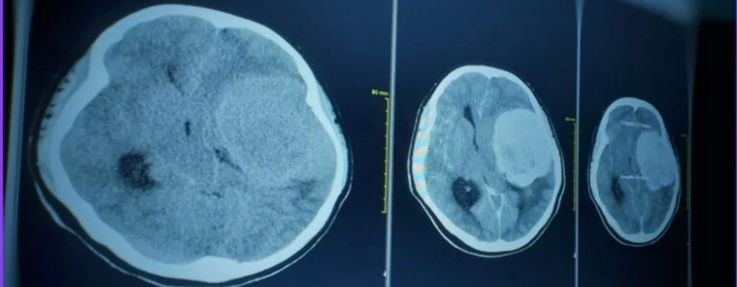

O Desafio do Diagnóstico por Imagem

A suspeita clínica deve ser investigada imediatamente com exames de imagem avançados. A Ressonância Magnética (RM) do crânio é o exame de escolha, pois fornece imagens detalhadas das estruturas cerebrais, permitindo identificar a localização exata, o tamanho e as características do tumor. Em alguns casos, a biópsia pode ser necessária para determinar o tipo exato de célula tumoral e guiar o tratamento.

A Microcirurgia Neurológica de Ressecção

O tratamento cirúrgico é a principal abordagem para a maioria dos tumores acessíveis. O objetivo é remover a maior quantidade possível do tumor com segurança, preservando as funções neurológicas vitais. Hoje, utilizamos tecnologias como a neuronaqueção e o monitoramento eletrofisiológico intraoperatório, que funcionam como um “GPS” para o cirurgião, aumentando a precisão e a segurança do procedimento.